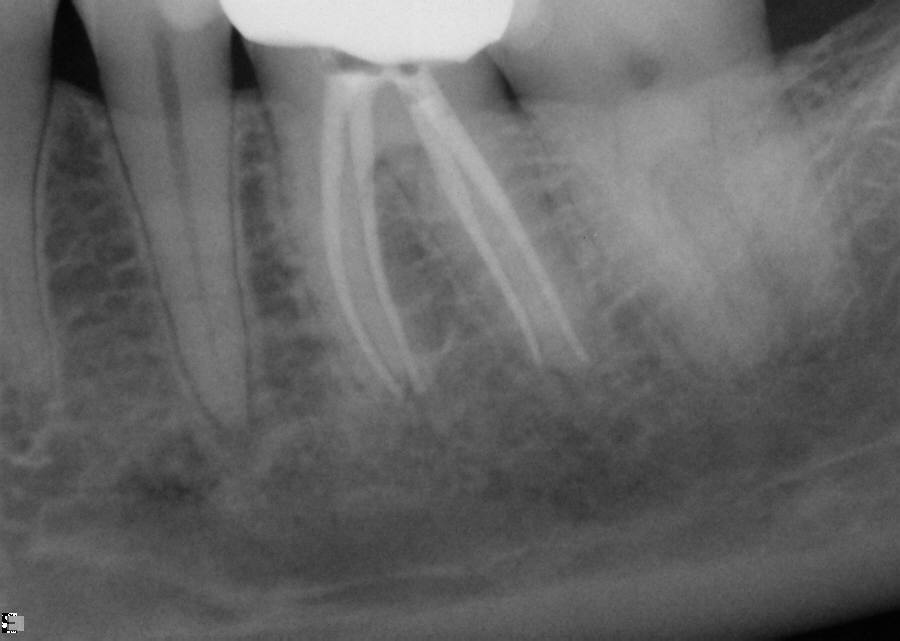

Excellent diagnosis essentially begins with two fundamental components: a doctor willing to listen to the patient’s chief complaint, and proper diagnostic tools. Among the most important tools are a precise periapical radiograph (PA) and bitewing (BW). Although a PA is often enough to provide an accurate portrayal of the patient’s condition, sometimes it alone does not suffice. Figure 1, Figure 2, and Figure 3 demonstrate a case that illustrates this point clearly. Despite two acceptable PAs (Figure 1 and Figure 2), it is difficult to assess the source of the patient’s pain to temperature. However, the BW radiograph Figure 3 provides significantly more clarity than either of the two PAs. The BW depicts localized bone loss (around tooth No. 2), a pulp stone (No. 2), a flat occlusion, numerous calcified canals, multiple restorations in tooth No. 30, and gross decay especially on tooth No. 3, which is the source of the patient’s pain to temperature. In this instance these images depict how much more useful a BW can be than just a conventional PA.